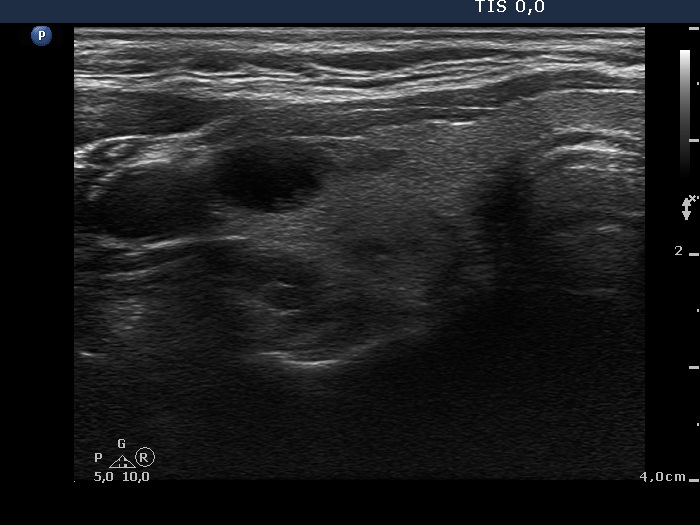

Ultrasonography: The thyroid was echonormal and contained several nodules with different echogenicities including a hypoechogenic one in the ventromedial part of the left lobe. This lesion presented a lobulated margin and a type 1 vascular pattern.